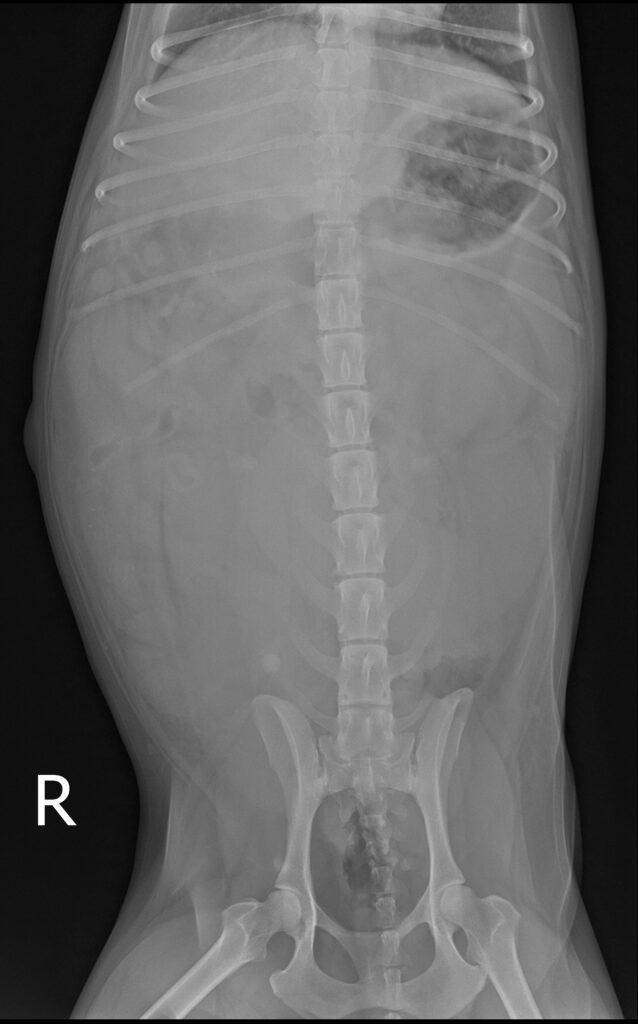

복부 방사선 검사 결과 / 출처: 24시온숲동물의료센터

복부초음파·방사선검사 결과

- 내원 당시 시행한 복부 초음파 및 방사선 검사에서 정상적으로는 4mm 정도 두께인 자궁이 약 4cm까지 심하게 확장되어 있는 모습이 확인되었습니다. 내부에는 고름으로 추정되는 내용물이 가득 차 있었으며, 이는 전형적인 자궁축농증의 소견에 해당합니다.